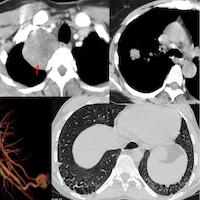

IgG4-related disease is an autoimmune process with infiltration of IgG4-plasma cells into tissues. It typically presents as a multi-organ, multicompartmental disease process.

The lung findings are myriad but often non-specific and it is not easy to make a prospective diagnosis, unless there are other organs like the lacrimal glands, salivary glands, pancreas, kidneys, aorta, etc involved.

This video goes through multi-system IgG4-related disease in general and then specifically looks at pulmonary and extra-pulmonary manifestations.